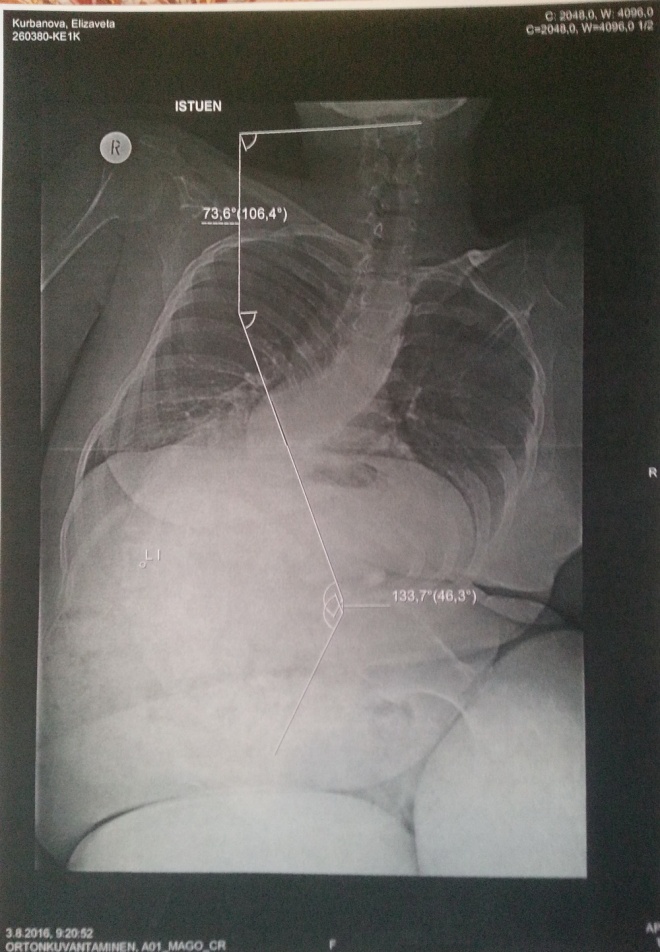

3 августа 2016 года я слетала туда и получила согласие финских хирургов на операцию. Вернувшись в Москву, я стала искать фонд, который мог бы помочь со сбором средств. Многие фонды мне отказывали именно по причине того, что операция в зарубежной клинике. А в одном из фондов мне порекомендовали обратиться в московский Центр Патологии Позвоночника, где, к моему удивлению, делают аналогичные операции. Я сразу съездила на прием к основателю Центра, известному нейрохирургу Андрею Николаевичу Бакланову. Андрей Николаевич повторил то же, что и его финские коллеги: если не сделать операцию, сколиоз будет прогрессировать и вскоре я не смогу не только сидеть, но и дышать. Причина болей в сильной деформации, которая составляет 134 градуса.